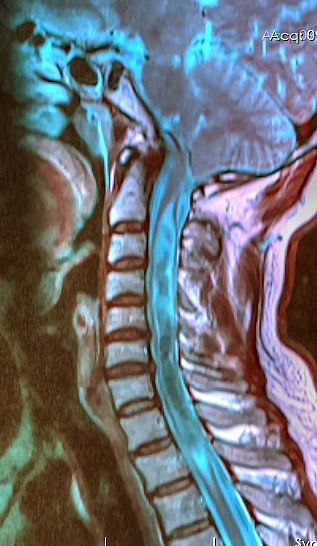

Arnold Chiari Malformation

Arnold-Chiari malformation is a condition in which the spinal canal is invaded by the lower section of the brain.

Arnold-Chiari malformation is a foramen magnum-based congenital expansion of the cerebellar tonsils.

Hydrocephalus may develop in Arnold-Chiari malformation as a result of cerebrospinal fluid (CSF) flow obstruction.

Arnold-Chiari malformation may present together with meningomyelocele or syringomyelia.

• Arnold Chiari Malformation

Arnold Chiari Malformation. Syringomyelia associated with Chiari malformation © Nevit Dilmen Dichromatic, False-color MRI. Cervical spine, T1 Red, T2, Green& Blue Permission details You may select the license of your choice. Not altered. CC BY-SA 3.0